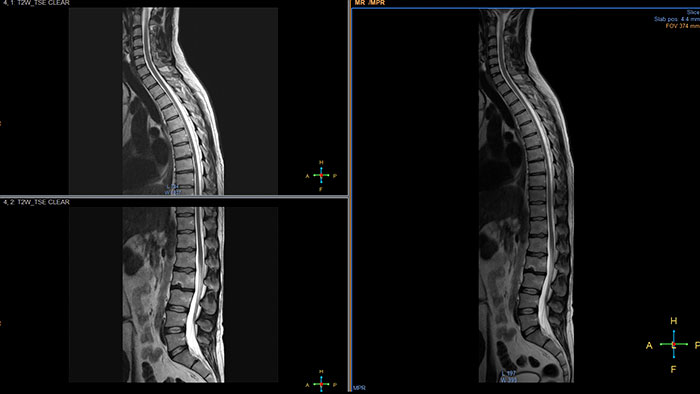

Visualize white matter connectivity in the brain

Provides visualization and quantification of white matter structure in the brain and spinal tracts using task guidance for generating common or user-defined tracts.

Gain an optimized view of the body’s most complex organ

Supports the visualization of brain images for the evaluation and monitoring of changes across multiple time points. The application performs automatic registration between studies and provides semi-automatic segmentation and editing tools for volumetric measurement of brain lesions.